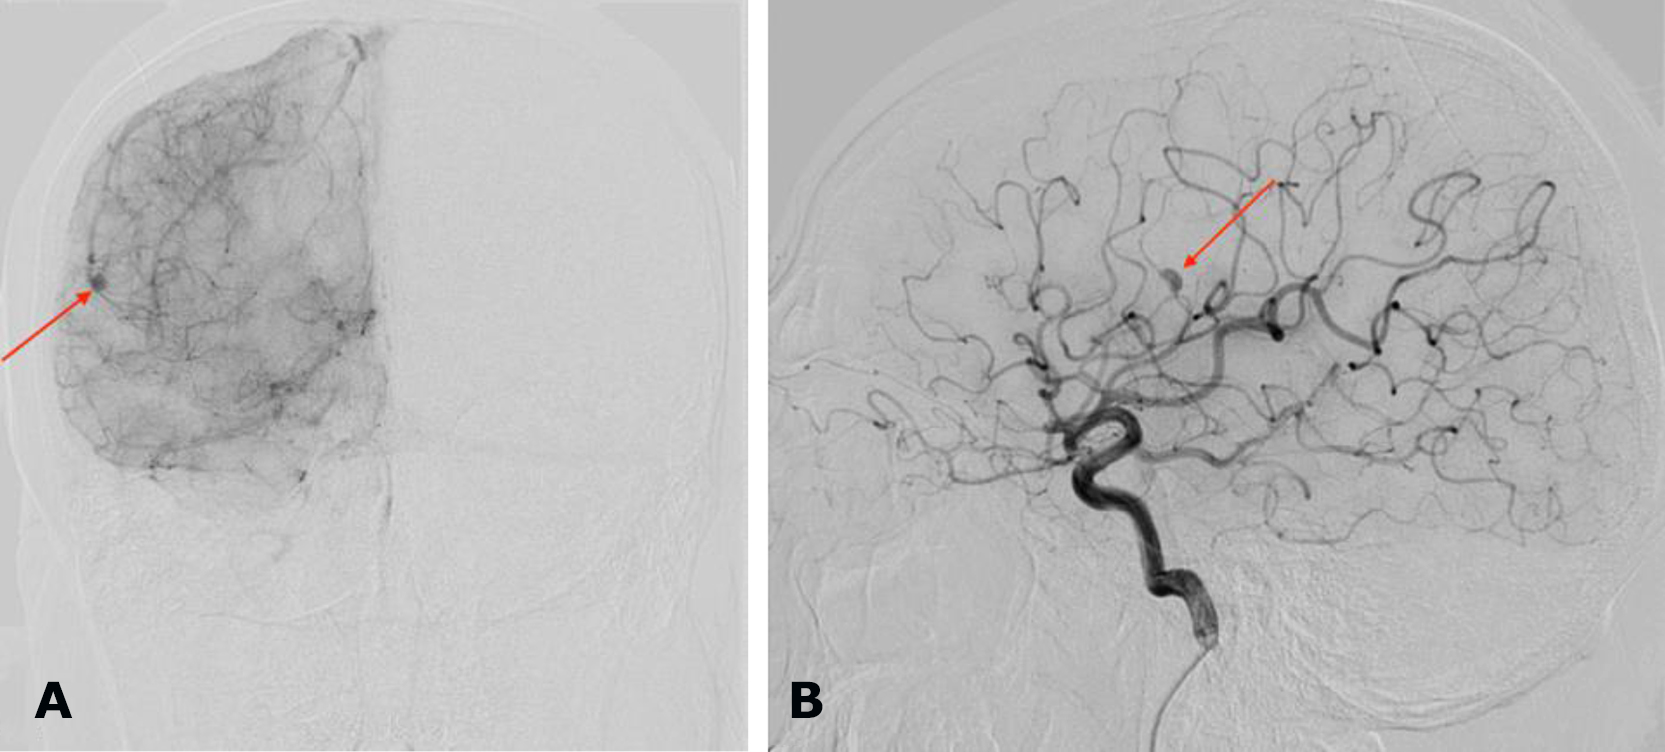

Brain MRI demonstrated a right-sided hemispheric multiloculated cSDH with dimensions (thickness/length/height) of 27/165/87 mm and a 5-mm midline shift to the left (Fig. 10).

Fig. 10. Preoperative brain MRI, T2 FLAIR sequence: A, B – axial projections demonstrating a right-sided hemispheric multiloculated cSDH

X-ray endovascular embolization of the right MMA using the Onyx™ embolic agent was performed on March 21, 2024 (Fig. 11).

Fig. 11. Intraoperative cerebral angiography. Right external carotid artery territory: A – left lateral projection, arterial phase; B – left lateral projection, arterial phase, superselective angiogram of the right MMA; C – left lateral projection, arterial phase, post-embolization state of the right MMA; D – angiogram in the left lateral projection without digital subtraction. The right MMA and its branches are indicated by a red arrow; the right maxillary artery by an orange arrow; the right external carotid artery by a light blue arrow; the microcatheter positioned within the right MMA by a green arrow; the radiopaque cast of the right MMA after Onyx™ embolization by a yellow arrow; and the hazardous anastomotic branches of the MMA by white arrows: 1—medial; 2—sphenoidal; 3—ramus meningolacrimalis

Follow-up brain MRI performed 6 months after surgery (Fig. 12) demonstrated complete resolution of the chronic subdural hematoma with restoration of the normal position of the midline brain structures. At follow-up examination, regression of global cerebral symptoms was noted.

Fig. 12. Postoperative brain MRI, T2 FLAIR sequence: A, B – axial projections demonstrating the absence of right-sided chronic subdural hematoma (cSDH)